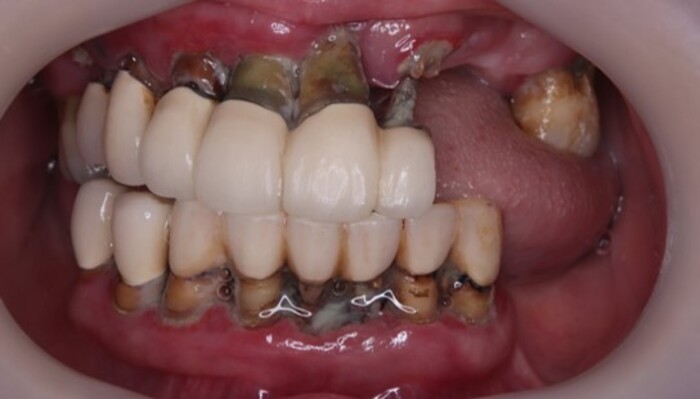

初診日:歯がボロボロ

| 現病歴 | 小さな時から歯が弱く、通っていた歯医者で歯を全部削られて、被せ物を入れられた。 それ以来歯を磨くのが難しくなり、日に日に歯が抜け落ちて、残った歯もグラグラで食べ物を食べるのも難しくなってきた。 他の歯科医院では、オールオン4しかないと言われたが、そこまでの費用を出せる余裕はないとのことでした。 |

上あごの左右6番目の歯を残して、それ以外は抜歯し、直ぐに入れ歯をセットして、調整を繰り返す。

半年後に2個目の入れ歯を製作するという治療計画を立てました。

最終的な入れ歯になります。かみ合わせも見た目もしっかりと合っていると思います。